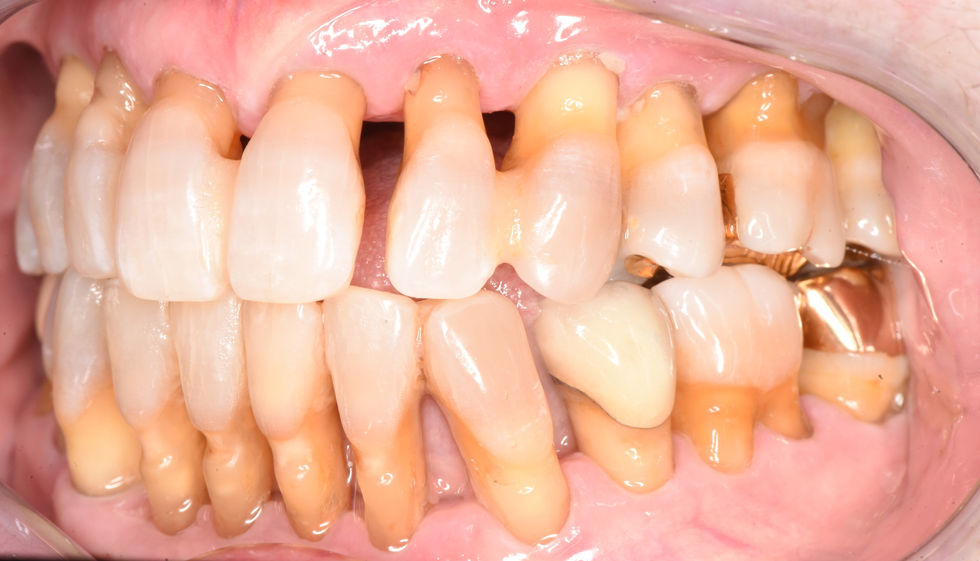

AOX W ceramic implants

AOX case full upper and lower

AOX upper and lower done with full ceramic screw retained implants w Yomi Robot guide.